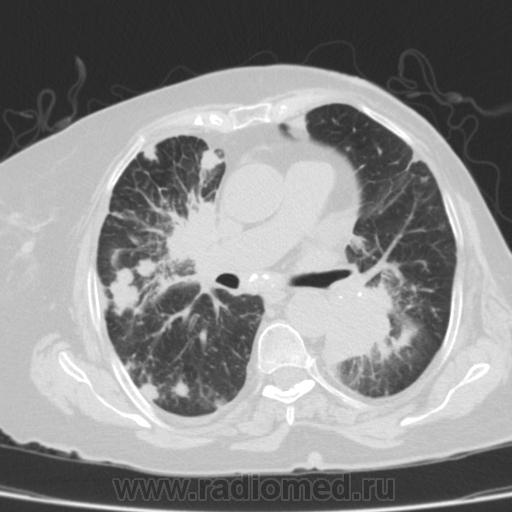

Метастатическое поражение легких.

Пожилая женщина, 76 лет находится на стац.лечении, провели СКТ дообследование.  Сопут- сr левой молочной железы. Такие множественные

поражения  в легких встречаются не часто.

Раннее несколько лет назад оперирована по поводу рака левой молочной железы.

Не всё на снимках видно. Многое осталось бы за кадром.